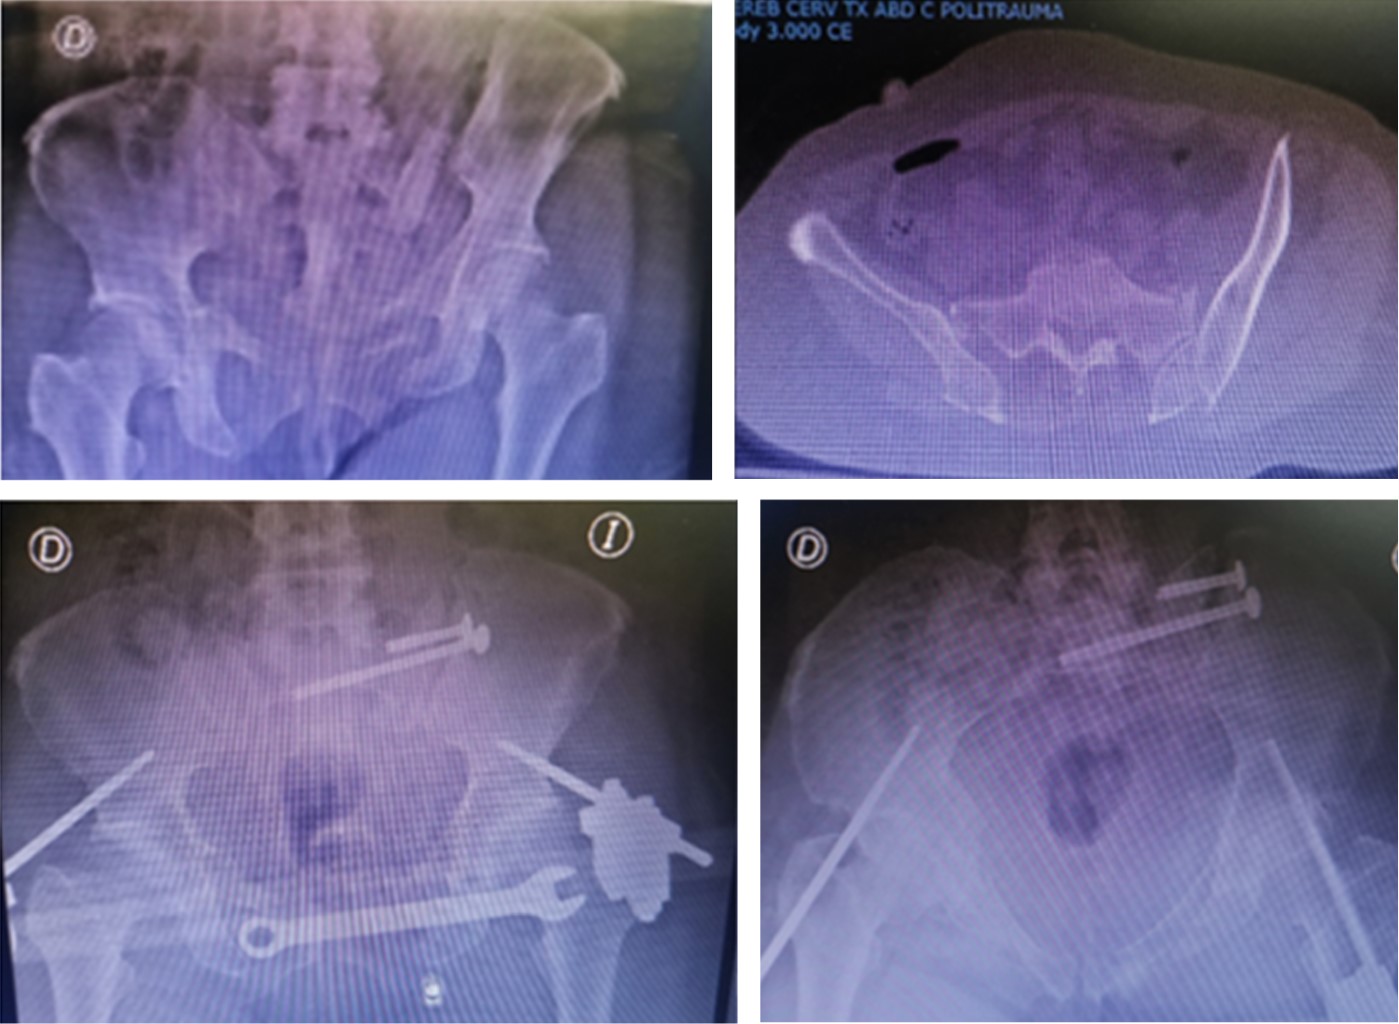

Tres pacientes fueron tratados secuencialmente con cirugía de control de daños (Figura 3) (con fijador supra-acetabular) y la osteosíntesis definitiva se realizó entre el tercero y octavo día de hospitalización.